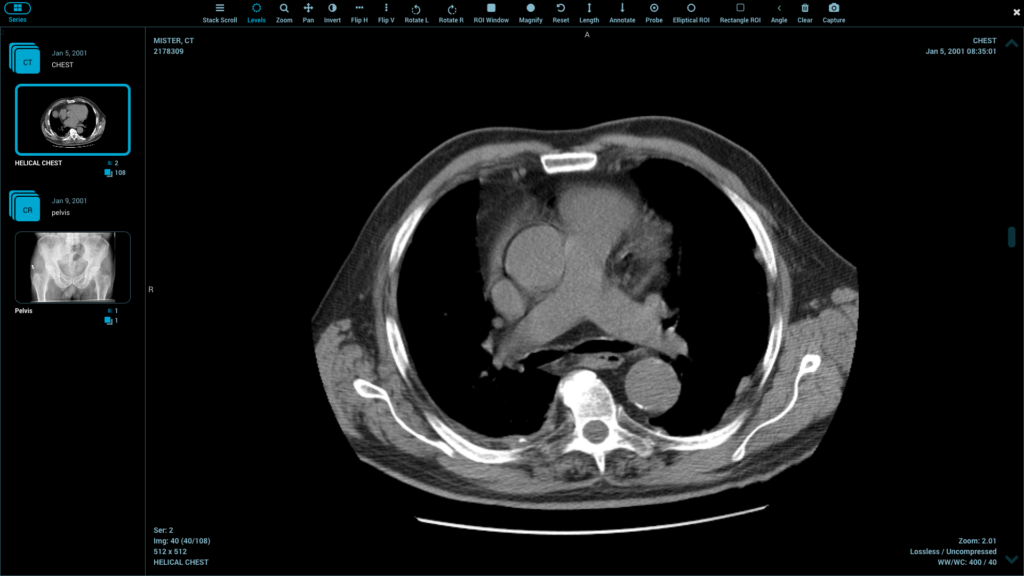

Healthcare software ecosystems are vital because of seamless integration. The components of the DICOM viewer library should be able to interface well with PACS and RIS platforms. Integration with electronic health records helps to facilitate single workflow.

API can be modified to meet other clinical requirements. It can be deployed across the desktop, web and mobile, and this is made possible by cross-platform support. Regular data management minimizes errors of integration.

Libraries that are compliant with standards make it easier to align with regulatory standards. Efficiency in integration decreases development time and effort put in maintenance.